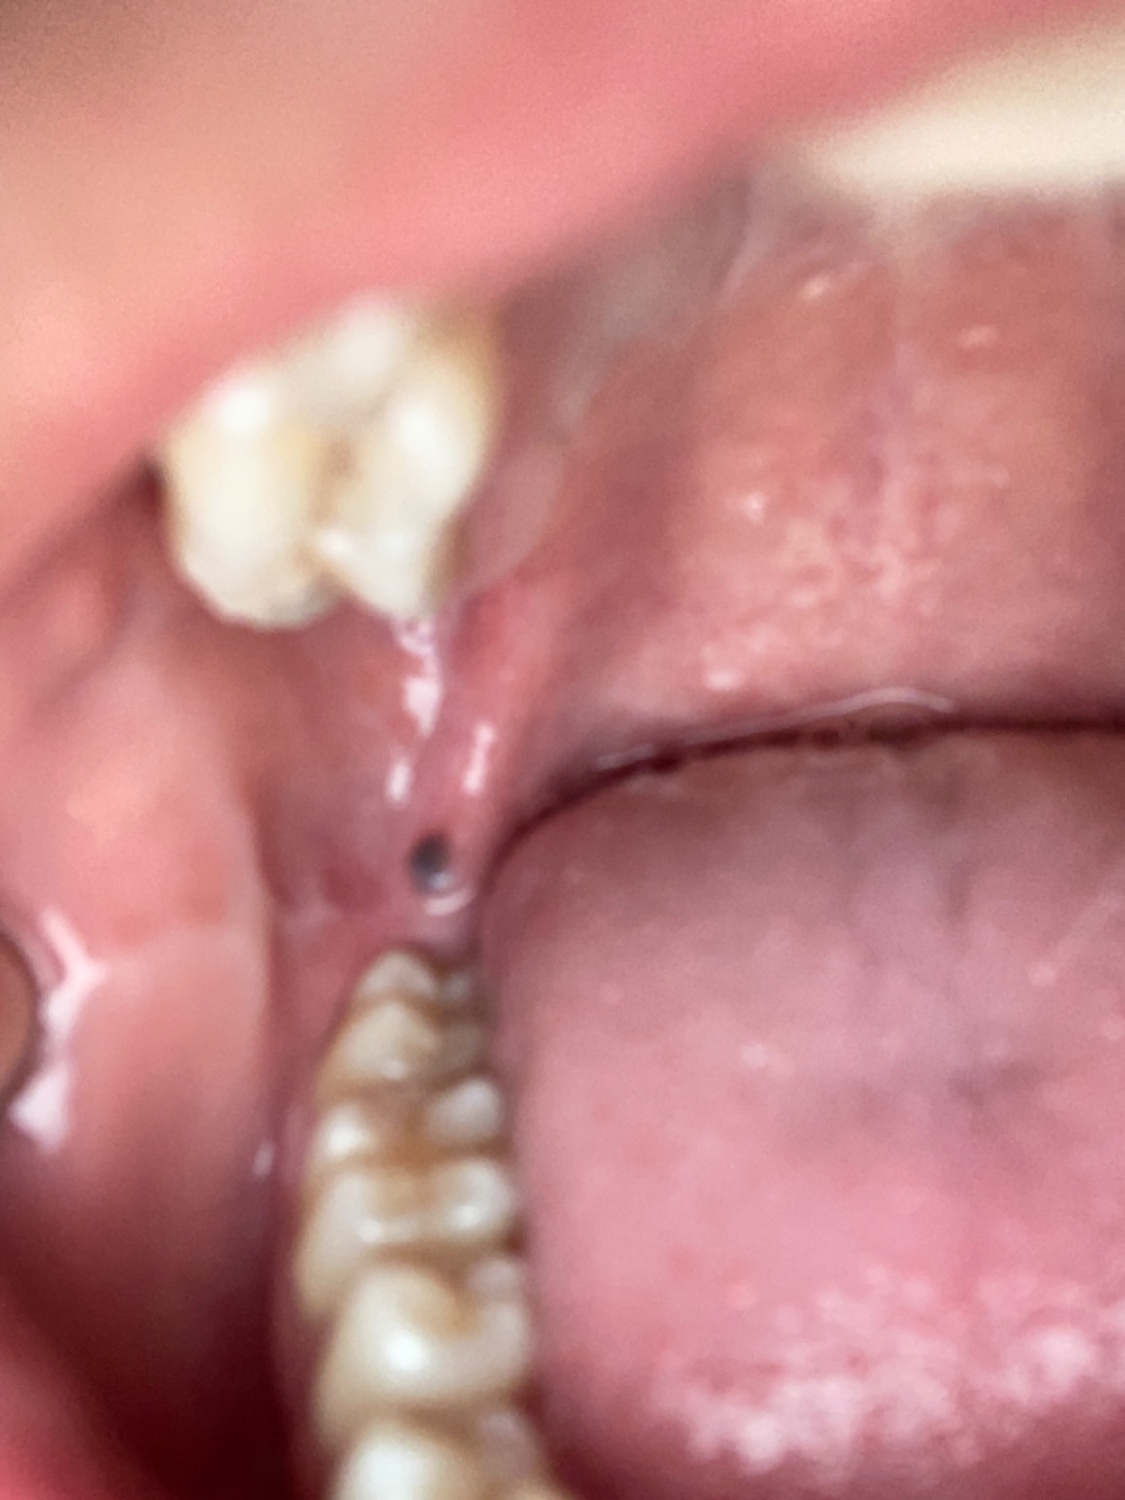

อยากสอบถามผู้รู้ว่าจุดสีดำนี้คืออะไรอันตรายไหม

ทันตกรรม